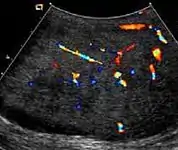

At ultrasound, the findings of acute epididymitis include an enlarged hypoechoic or hyperechoic (presumably secondary to hemorrhage) epididymis [Fig. 20a]. Other signs of inflammation such as increased vascularity, reactive hydrocele, pyocele and scrotal wall thickening may also be present. Testicular involvement is confirmed by the presence of testicular enlargement and an inhomogeneous echotexture. Hypervascularity on color Doppler images [Fig. 20b] is a well-established diagnostic criterion and may be the only imaging finding of epididymo-orchitis in some men.